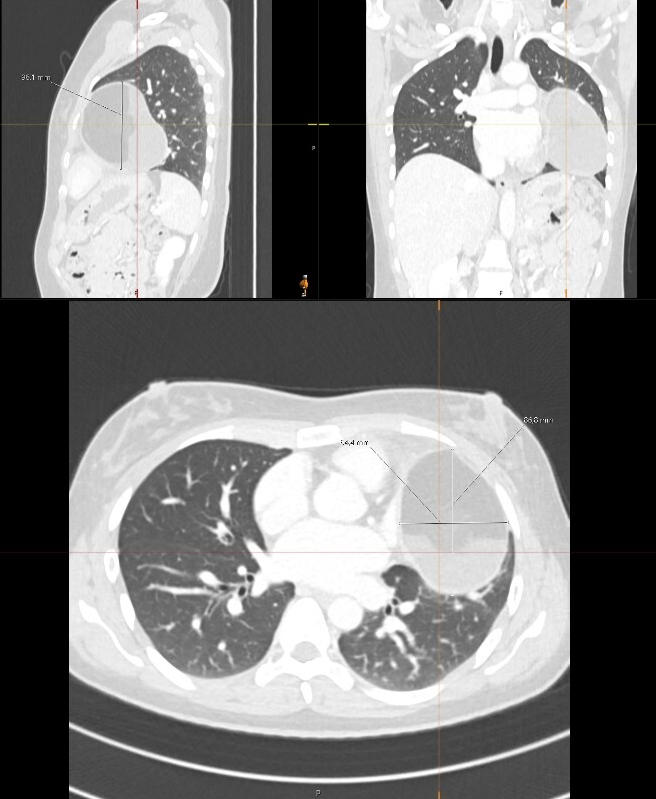

Hoe wordt een tumor in het mediastinum ontdekt?

Meestal wordt de tumor gezien op een röntgenfoto of CT-scan van de borstkas. Daarna volgen vaak een MRI of PET-scan (voor uitbreiding en activiteit), soms een Biopsie: om te bepalen wat voor soort tumor het is en vrijwel altijd bloedonderzoek: soms met tumormarkers.